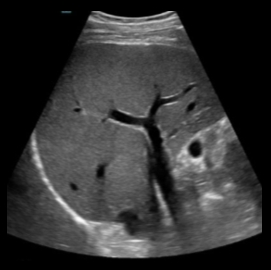

2D image of liver visualized with a convex transducer

A convex transducer is a curved transducer. The shape of a convex transducer determines the sector width and shape of the image. A convex transducer offers a wider field of view for larger or deeper structures. Convex transducers are most frequently used for abdomen, obstetrics/gynecology (OB/GYN), urology, and some musculoskeletal (MSK) applications.